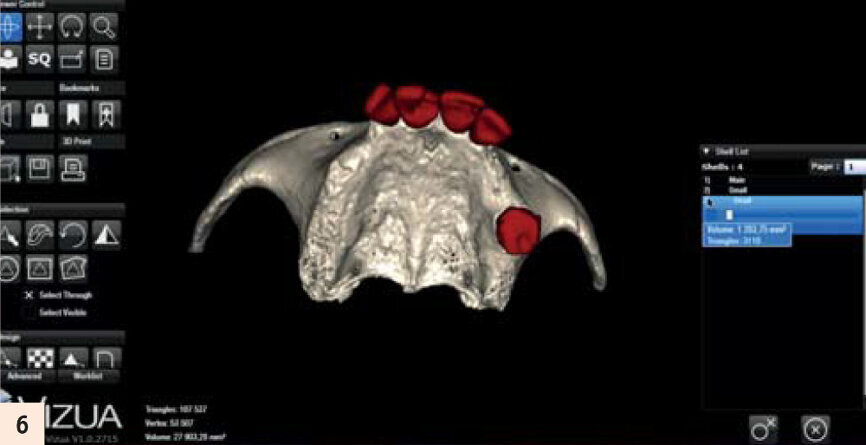

Modélisation par Vizua du modèle denté...

L’important est de reproduire par l’empreinte en fin de chirurgie, l’occlusion enregistrée des semaines auparavant. La technique utilisée sera l’empreinte fractionnée, grâce à une gouttière callée sur des repères fixes que nous retrouvons en fin d’intervention (Fig. 5). Cette méthode a été décrite par Luc Gillot et Bernard Cannas qui font partie des pionniers de la MCI en France.9, 11 Ce cas clinique est complexe. Comme toute chirurgie, nous n’avons pas le droit à l’erreur. La planification sur ordinateur a permis de se familiariser avec les volumes osseux. Simuler la chirurgie permettrait d’éviter les pièges d’une anatomie complexe. En partenariat avec l’équipe Vizua et la Sapo implant, nousimprimons le maxillaire de notre patiente en individualisant les dents pour visualiser les alvéoles d’extraction (Figs. 6 et 7). Puis nous procédons au forage dans ce modèle imprimé en résine, en suivant notre planification. Nous appréhendons les difficultés de ce cas : la fine corticale du bloc incisif, la position exacte de l’implant en 15 dans la paroi antérieure du sinus droit... Quelle meilleure préparation que la simulation sur modèle ? (Fig. 8)